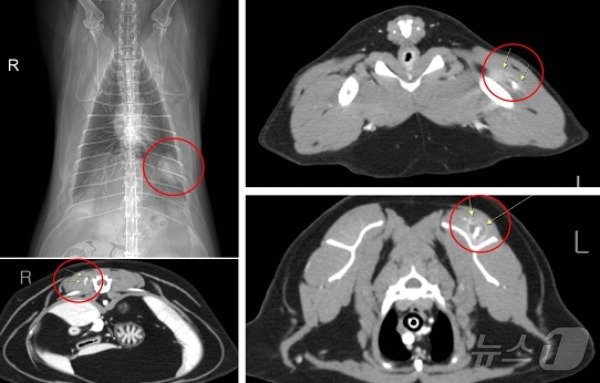

본문 이미지 - 고양이 마취 전 검사 시 흉부방사선사진과 전신 CT검사에서 발견된 종양(고려동물메디컬센터 고양이병원 제공) ⓒ 뉴스1

고양이 마취 전 검사 시 흉부방사선사진과 전신 CT검사에서 발견된 종양(고려동물메디컬센터 고양이병원 제공) ⓒ 뉴스1